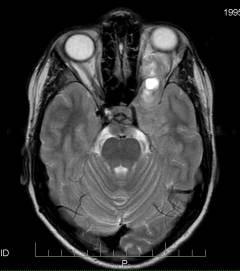

Признаки саркомы мозга, выявляемые при инструментальных исследованиях:

- КТ:

- неоднородная опухоль с размытыми границами

- если опухоль расположена на оболочках мозга, может иметь четкие контуры

- признаки прорастания саркомы в мозговую ткань

- метастазы в легких и костях